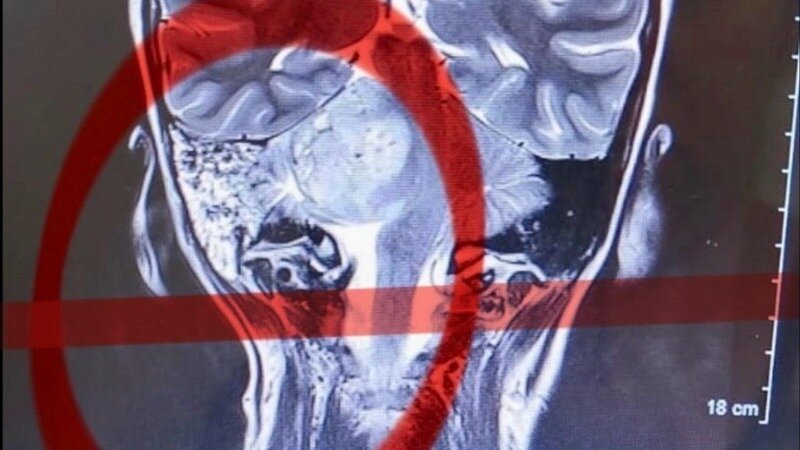

Alzheimer, AVC, tumeurs cérébrales : explorons enfin la piste des contractures cervicales